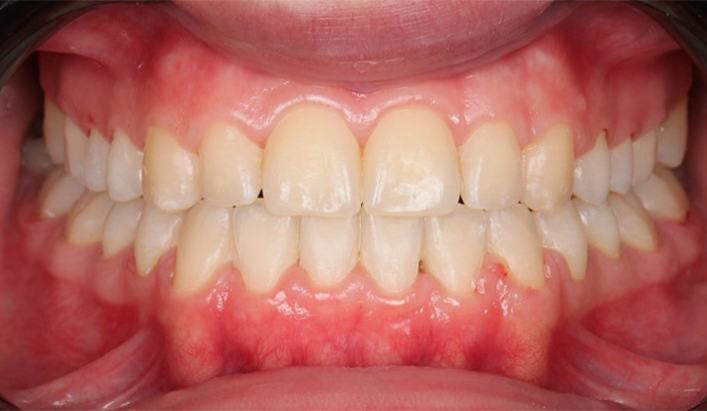

At the end of treatment, the patient’s occlusion was corrected to Class I molar and canine relationships with a physiological overjet and overbite. Irregularities in both arches were eliminated, arch forms were coordinated, and incisor torque was effectively controlled to position the roots centrally within the alveolar bone, enhancing stability. Satisfactory intercuspation was achieved in both the anterior and posterior segments, with maintenance of midline coincidence and periodontal health throughout treatment. The case was finished and transitioned into the retention phase using fixed retainers in the maxillary and mandibular anterior regions.

This case demonstrates that, in the Damon Ultima system, appropriate torque selection provides a rapid and efficient treatment modality, offering enhanced biomechanical control for the clinician and a shorter, more comfortable treatment experience for the patient. In particular, root movements and the finishing phase, which require meticulous management in Class III cases, were completed in a predictable and efficient manner, with high levels of comfort for both the clinician and the patient through the use of carefully selected torque prescriptions.